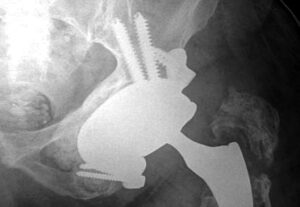

Le comuni protesi disponibili sul mercato non erano adatte al caso e per questo è stato necessario procedere, tramite il ricorso alla tecnologia, alla ricostruzione di un impianto su misura. Un pool di ingegneri biomedici, mediante un software, ha elaborato un progetto che è stato discusso con i chirurghi i quali hanno simulato l’intervento al computer, lavorando su forma e dimensione di ogni componente protesica, alla luce delle caratteristiche anatomo-patologiche della paziente. Si è così passati alla realizzazione della protesi tramite la moderna tecnologia a stampa 3D in titanio trabecolato e, infine, all’intervento chirurgico per impiantarla.

In sala operatoria sono state realizzate delle riproduzioni tridimensionali in plastica del bacino e dell’impianto per le valutazioni di prova delle componenti. Per la ricostruzione è stato necessario anche l’utilizzo di innesti ossei da banca dell’osso. L’intervento è durato circa 3 ore e si è svolto senza complicanze. Pochi giorni dopo l’operazione, la paziente ha ripreso a deambulare grazie a un percorso di riabilitazione intensiva ed entro 2-3 mesi potrà tornare a svolgere una vita normale.